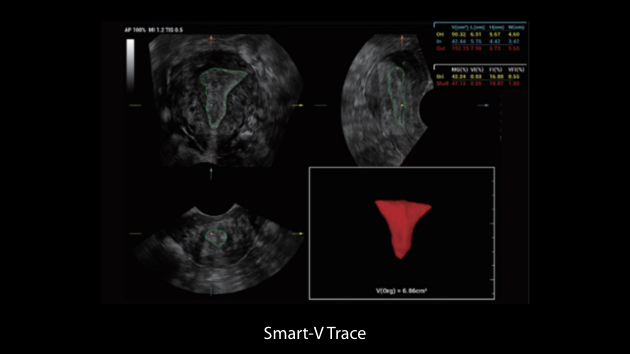

Le Nuewa?I9, con?u spÃĐcialement pour la santÃĐ de la femme et les soins nÃĐonataux, offre une expÃĐrience entiÃĻrement nouvelle gr?ce aux innovations dont il est dotÃĐ, tant à lâintÃĐrieur quâà lâextÃĐrieur. Ces innovations sont dÃĐveloppÃĐes sur la base d'une comprÃĐhension approfondie de scÃĐnarios cliniques complexes, fournissant des rÃĐponses prÃĐcises et adaptÃĐes ainsi qu'une efficacitÃĐ exceptionnelle et une expÃĐrience utilisateur remarquable.

La plate-forme ZST+?est une innovation extraordinaire, reprÃĐsentant une ÃĐvolution de lâimagerie ultrasonore. Elle transforme la formation conventionnelle de faisceaux en un traitement basÃĐ sur les canaux de donnÃĐes. Elle repousse les limites de lâimagerie conventionnelle et du compromis entre rÃĐsolution spatiale, rÃĐsolution temporelle et uniformitÃĐ tissulaire en offrant une qualitÃĐ dâimage exceptionnelle pour des solutions dâimagerie infinies et en constante ÃĐvolution.